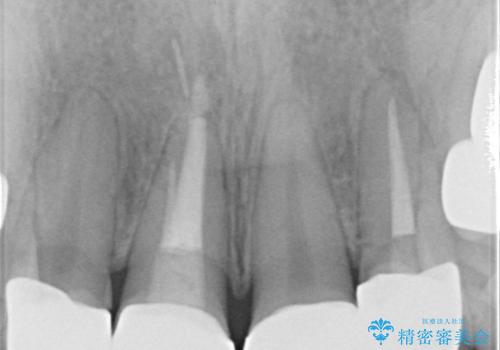

- 子供の頃にジュースが原因で虫歯が多発し、レジン修復をしていたが見た目の改善を希望され来院されました。

レジン充填・虫歯を丁寧に全て除去したのちジルコニアセラミックを用いた前歯の審美改善を計画します。

- 52.8万円(ジルコニアクラウン×4・仮歯×4)費用は治療当時の料金となります